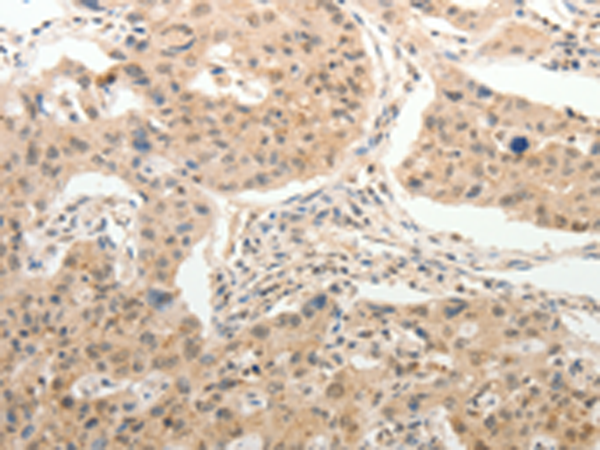

分类: 科研抗体货号: P11170别名: PAQR2; ACDCR2应用: IHC反应种属: Human, Mouse